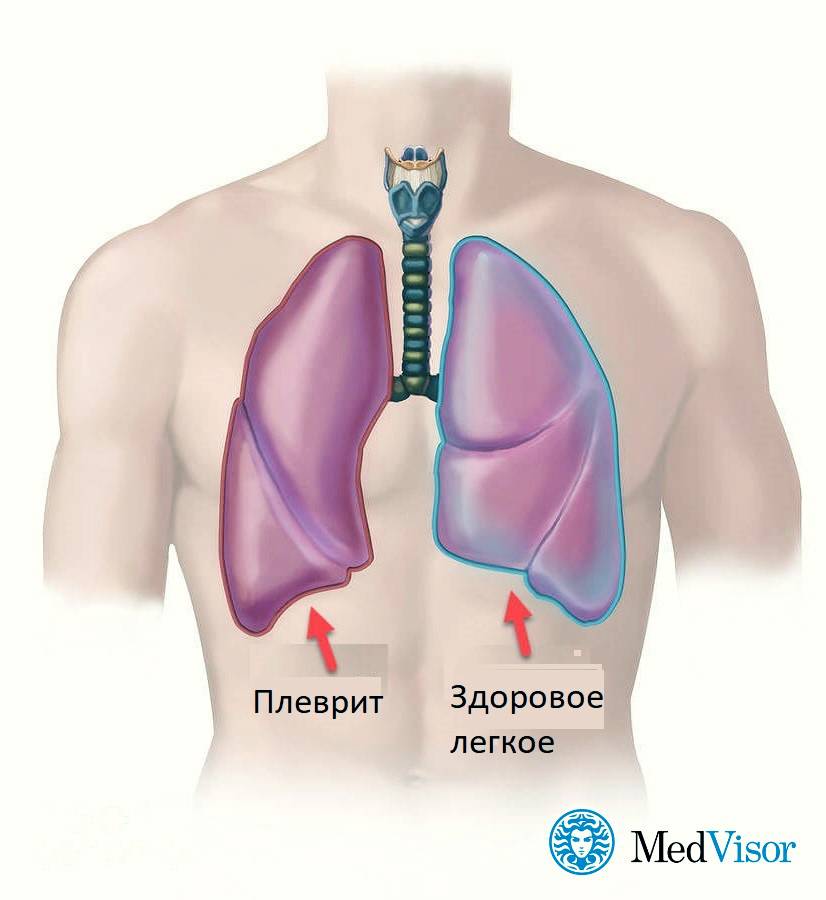

Диагностика плеврального выпота: что нужно знать